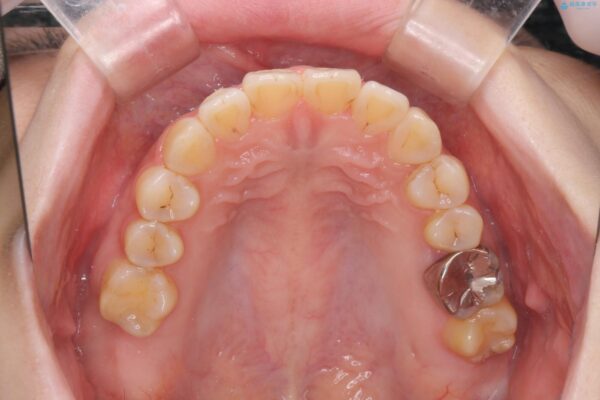

治療前

傾いた前歯、インビザラインで改善 治療前画像 傾いた前歯、インビザラインで改善 治療前画像 傾いた前歯、インビザラインで改善 治療前画像 傾いた前歯、インビザラインで改善 治療前画像